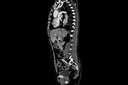

O exame do líquor1 pode ajudar a diagnosticar uma série de doenças. Para isso, é necessário obter uma amostra desse fluido, através de uma punção em quatro vias possíveis: lombar, suboccipital, ventricular e cervical lateral.

A punção lombar, a mais comum, é feita por meio da inserção de uma agulha na região lombar14 abaixo da terminação da medula espinhal4, ao nível do saco dural. A aparência do líquor1 assim obtido já pode sugerir algumas enfermidades. Sua aparência normal é descrita como “água de rocha”. Uma aparência turva pode indicar uma inflamação15, provavelmente uma meningite16, a presença de sangue10 no líquido pode indicar uma hemorragia17 no cérebro3 ou ao redor dele, etc.